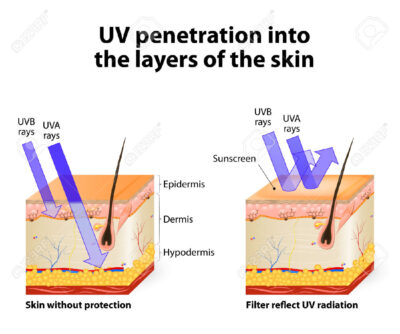

Secondo il The Skin Cancer Foundation i raggi ultravioletti (UV) sono la causa primaria del carcinoma basocellulare e carcinoma a cellule squamose e Liang e colleghi affermano che l’esposizione ai raggi UV è la causa di oltre il 90 per cento dei melanoma.

Le radiazioni UV – da raggi solari e lettini abbronzanti e lampade – danneggiano il DNA delle cellule della pelle e possono causare mutazioni genetiche che portano al cancro della pelle.